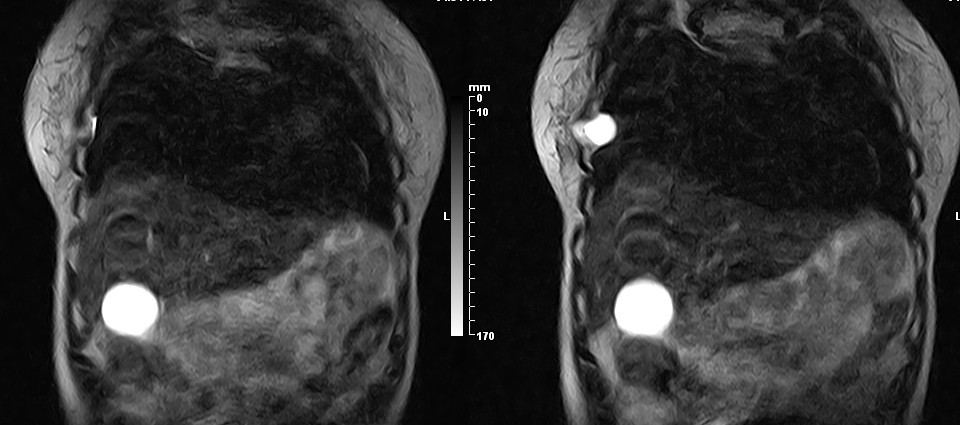

女,49岁。三年前因胸部不适在外院行CT检查诊断报告:右胸壁占位病变,考虑胸膜间皮瘤可能性大。现病人到我院检查了解情况。算是较典型的病变吧?大家看看MR比CT优点在哪里?

病检神经鞘瘤

病检是神经鞘瘤。

液性信号符合神经鞘瘤囊变。